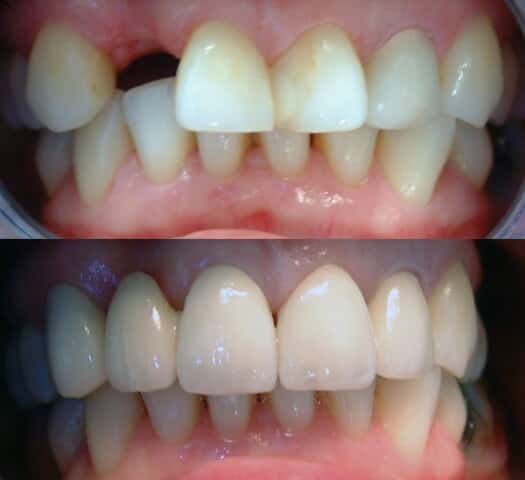

Crown